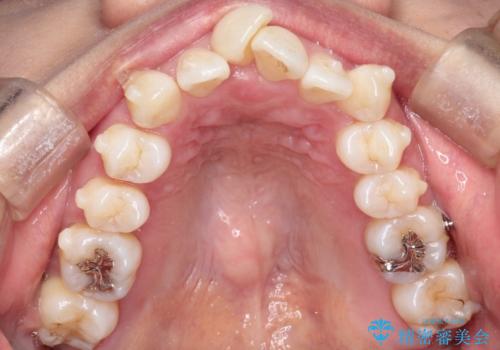

重度のガタガタのインビザラインによる非抜歯矯正

- 上下の歯のガタガタを主訴に来院されました。

インビザラインで奥歯を後方に移動させるのと、歯と歯の間をわずかに削ることでスペースを作り、歯を並べる計画としました。